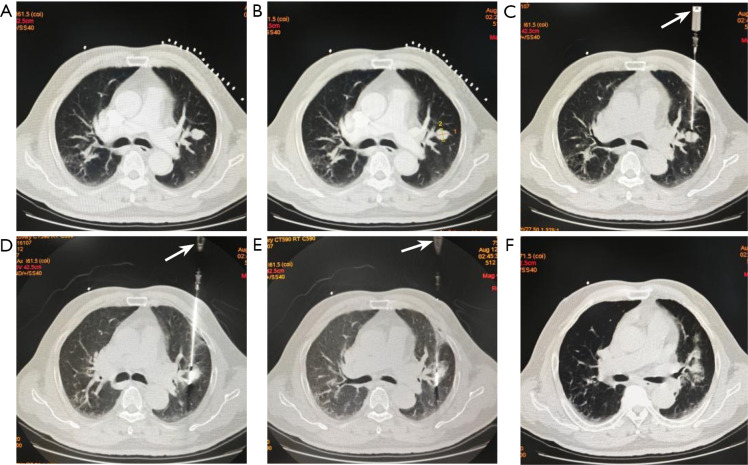

Methods: From January 2021 to December 2024, 91 patients with single highly suspected malignant PNs underwent synchronous MWA combined with PB. A total of 56 patients in group A underwent synchronous MWA followed by PB (MWA-first group) and 35 cases in group B underwent synchronous PB followed by MWA (PB-first group). The technical success, pathologically positive diagnosis rate, complications, and efficacy of the two groups were compared.

Results: The differences in technical success rate (100% vs. 97.1%) and positive pathologic diagnosis rate (80.4% vs. 88.6%) between group A and group B were not statistically significant (P>0.05). The most common complications included pneumothorax, intrapulmonary hemorrhage, hemoptysis, and pleural effusion. The incidence of intrapulmonary hemorrhage was significantly lower in group A than in group B (19.6% vs. 42.8%, P<0.05). The median follow-up time was 18.0 months, the local control rate was 98.8%, and the complete ablation (CA) rate was 56.6%.

Conclusions: Synchronous MWA combined with PB is a safe and effective strategy. MWA followed by PB could reduce the impact of intrapulmonary hemorrhage on ablation outcomes and is an alternative treatment for highly suspected malignant PN.